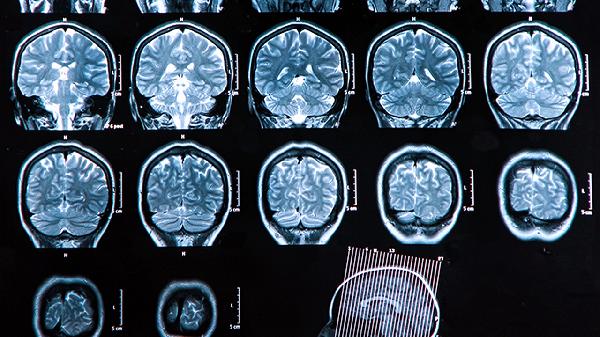

肿瘤压迫颅底神经可导致复视、面部麻木、听力下降等表现。例如侵犯海绵窦会引起动眼神经麻痹,表现为眼睑下垂;累及三叉神经可致面部感觉异常。症状与受累神经相关,需通过颅脑MRI明确病变范围。甲钴胺片、维生素B1片等神经营养药物可能有助于功能恢复。

颅骨转移瘤可在头皮触及固定质硬的肿块,伴局部压痛或皮肤红肿。乳腺癌转移常形成溶骨性破坏,前列腺癌转移则以成骨性改变为主。X线或CT显示骨质破坏伴软组织影,必要时需活检鉴别原发灶。双膦酸盐类药物如唑来膦酸注射液可延缓骨破坏进展。